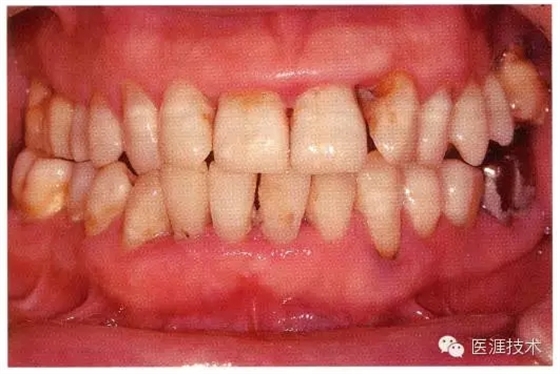

55歲牙周炎男性的臨床照片

55歲男性抽煙患者(1天20支、抽煙35年)。菌斑控制得不好。通過牙周探診,全頜有4~9mm的牙周袋,有1~3度的根分叉部病變。通過X光片觀察,上頜前牙中度牙槽骨吸收,其他地方有中度牙槽骨吸收。受吸煙影響,牙齦纖維性肥厚,呈紅黑色。牙齦幾乎沒有浮腫和發(fā)紅,所以這個病例是從外觀上無法預(yù)測病癥嚴(yán)重程度的病例。